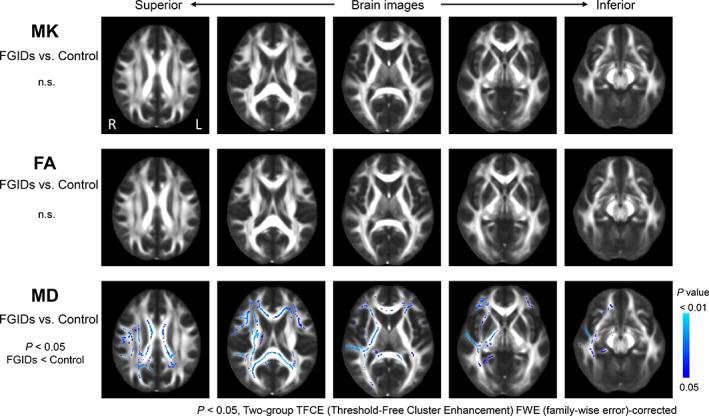

Twelve patients with FGIDs fulfilling the Rome IV criteria, and seven healthy controls were examined using a 3 T magnetic resonance (MR) scanner. Tract-based spatial statistics and regions of interest analyses were performed to compare the mean kurtosis (MK), fractional anisotropy (FA), and mean diffusivity (MD) between patients with FGIDs versus controls. HRQOL was assessed in patients with FGIDs using the eight-item short form of the Medical Outcome Study Questionnaire (SF-8) and the Gastrointestinal Symptom Rating Scale.

Patients with FGIDs had extensive, widespread regions of reduced MD in the white matter in comparison with healthy controls, whereas no significant differences were observed in MK and FA. No significant differences in deep gray matter for the MK, FA, and MD values were observed between patients with FGIDs and controls. In patients with FGIDs, the FA values in the globus pallidus had a significant and negative correlation with SF-8 (a mental component summary) ( = -0.797, = 0.01 uncorrected for multiple comparisons).

与健康对照相比,FGIDs患者白质中MD降低的区域广泛且分布广泛,而MK和FA未观察到显著差异。FGIDs患者与对照组之间在深部灰质的MK、FA和MD值方面未观察到显著差异。在FGIDs患者中,苍白球的FA值与SF-8(心理成分总结)呈显著负相关(=-0.797,=0.01,未进行多重比较校正)。